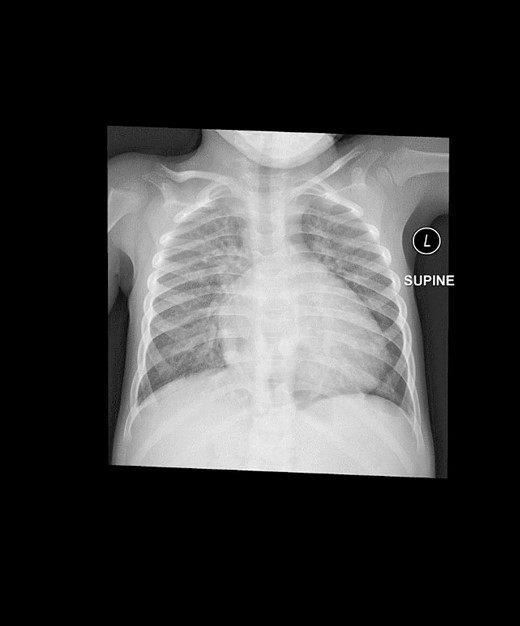

Post-surgery, the patient was transferred to the Pediatric Cardiac Intensive Care Unit in stable condition. Follow-up chest X-rays confirmed successful repair of the diaphragmatic hernia (Fig. 3). However, 3 weeks later, the patient developed intermittent complete heart block. An electrophysiological assessment confirmed the need for a pacemaker, and a VVI pacemaker was implanted in the left epigastric area. The procedure involved creating a pocket under the left rectus muscle, entering the pericardium through the left chest, and implanting a bipolar electrode tunneled to the pocket. The pacemaker was successfully connected and placed, showing favorable threshold and impedance values.

This is a postoperative AP view of chest X-ray showing the disappearance of the abnormal mediastinal lucency representing loops of bowel.